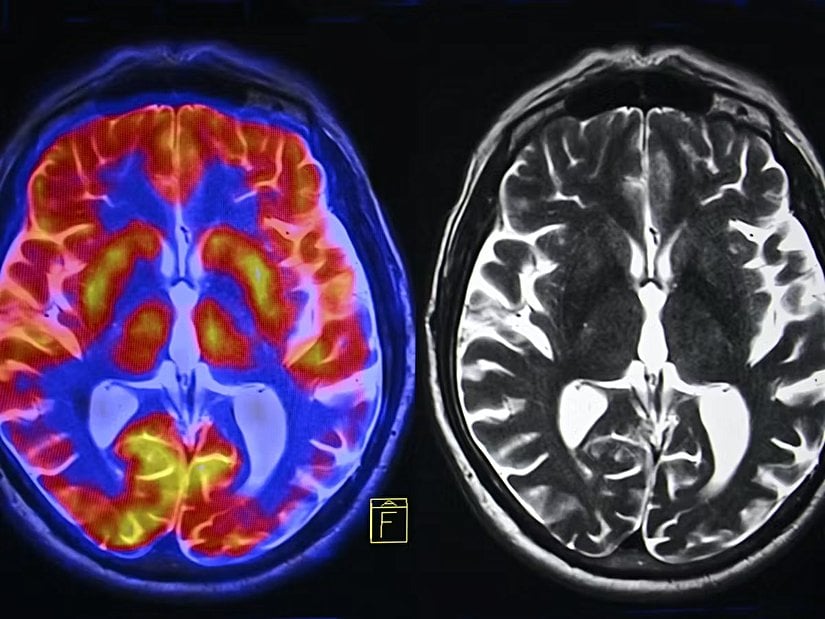

Araştırmayı gerçekleştiren bilim insanları, stresin beynin tokluğa verdiği doğal tepkiyi geçersiz kıldığını ve daha lezzetli yiyecekler yemeyi teşvik eden kesintisiz ödül sinyallerine yol açtığını tespit ettiler. Beynin "lateral habenula" isimli kısmında gerçekleşen ve aktive olduğunda genellikle ödül sinyallerini baskılayan sinyaller hakkında araştırmanın kıdemli yazarı ve Garvan Enstitüsü'nde ziyaretçi bilim insanı olarak çalışan Profesör Herzog şöyle söylüyor:

Normalde beynin ödül tepkisini kapatmakla ilgilenen ve lateral habenula olarak bilinen bölgenin, kısa sürede yüksek yağ alınan bir diyetle beslenen farelerde hayvanı aşırı yemekten korumak için aktifleştiğini keşfettik. Ancak, kronik stres altındayken beynin bu kısmı pasifti ve ödül sinyallerinin aktif kalmasına ve haz için beslenmeyi teşvik etmesine izin verdi. Yüksek yağ içeren diyetlerle beslenen stresli farelerin aynı diyetle beslenen stresli olmayan farelere göre iki kat daha fazla kilo aldığını bulduk.

Araştırmayı yürüten ekip, kilo alımının merkezinde beynin strese doğal yanıt olarak ürettiği NPY molekülünün olduğunu keşfetti. Yüksek yağlı bir diyet takip eden stresli farelerde NPY molekülünün lateral habenula bölgesindeki beyin hücrelerini aktive etmesi engellendiğindeyse fareler daha az konfor besini tükettiler; bu da daha az kilo alımıyla sonuçlandı.